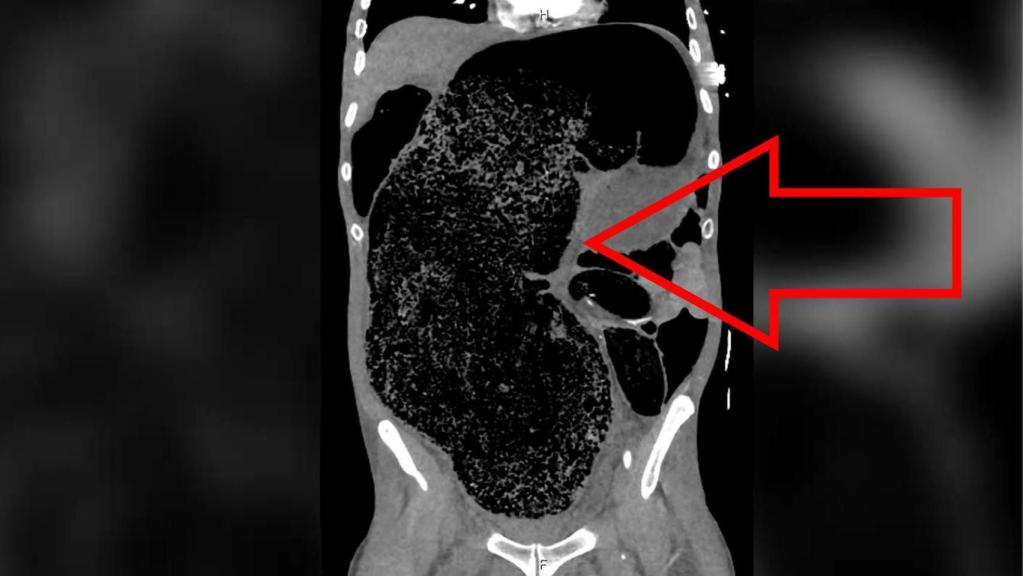

La masa fecal vista en el corte longitudinal, y la presión sobre las arterias. BMJ Case Reports

En este caso, la compactación había llegado al punto de provocar la distensión de su intestino grueso y abdomen, y la enorme masa impactada presionaba contra su arteria ilíaca derecha, provocando la isquemia responsable de cortar el riego a su pierna. También sufría síntomas de fallo renal y acidosis metabólica -una acumulación perniciosa de ácido- que determinaron una intervención quirúrgica inmediata.

"Se procedió a una desimpactación manual de emergencia bajo anestesia general mediante la cual se extrajeron aproximadamente dos litros de heces" - describe el equipo liderado por los doctores Simon Ho, Russel Krawitz y Bill Fleming. Cuatro días después, el paciente pudo abandonar la planta de cuidados intensivos para ser tratado con laxantes. La recuperación completa y el poder caminar sobre sus propio pie no llegó hasta dos semanas después.